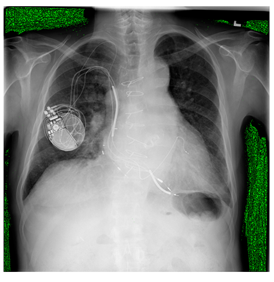

Breast-MRI-NACT-Pilot is an MRI-type image database, collecting breast medical images of 64 patients. Some samples are shown in Figure 12a.

Figure 12.

Sampled images in the tested benchmark databases: (a) Breast-MRI-NACT-Pilot (breast), (b) ACRIN-DSC-MR-Brain (brain), (c) NIH (chest), (d) Lung-PET-CT-Dx (lung), (e) Prostate-MRI (prostate), and (f) Other grayscale standard images.

ANIH is an X-ray type image database collecting chest medical images. Some samples are shown in Figure 12c.